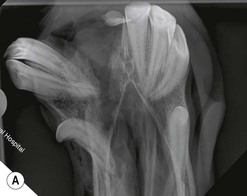

Fig. 13.20 (A) Intra-oral radiograph of a maxillary cheek teeth row.

Radiograph courtesy of J. Easley.

image

(B) Intra-oral radiograph taken intra-operatively during a dental extraction procedure. A small bone-opacity fragment can be seen in the rostral aspect of the alveolus (arrow).

(Radiograph courtesy of W.H. Tremaine.)